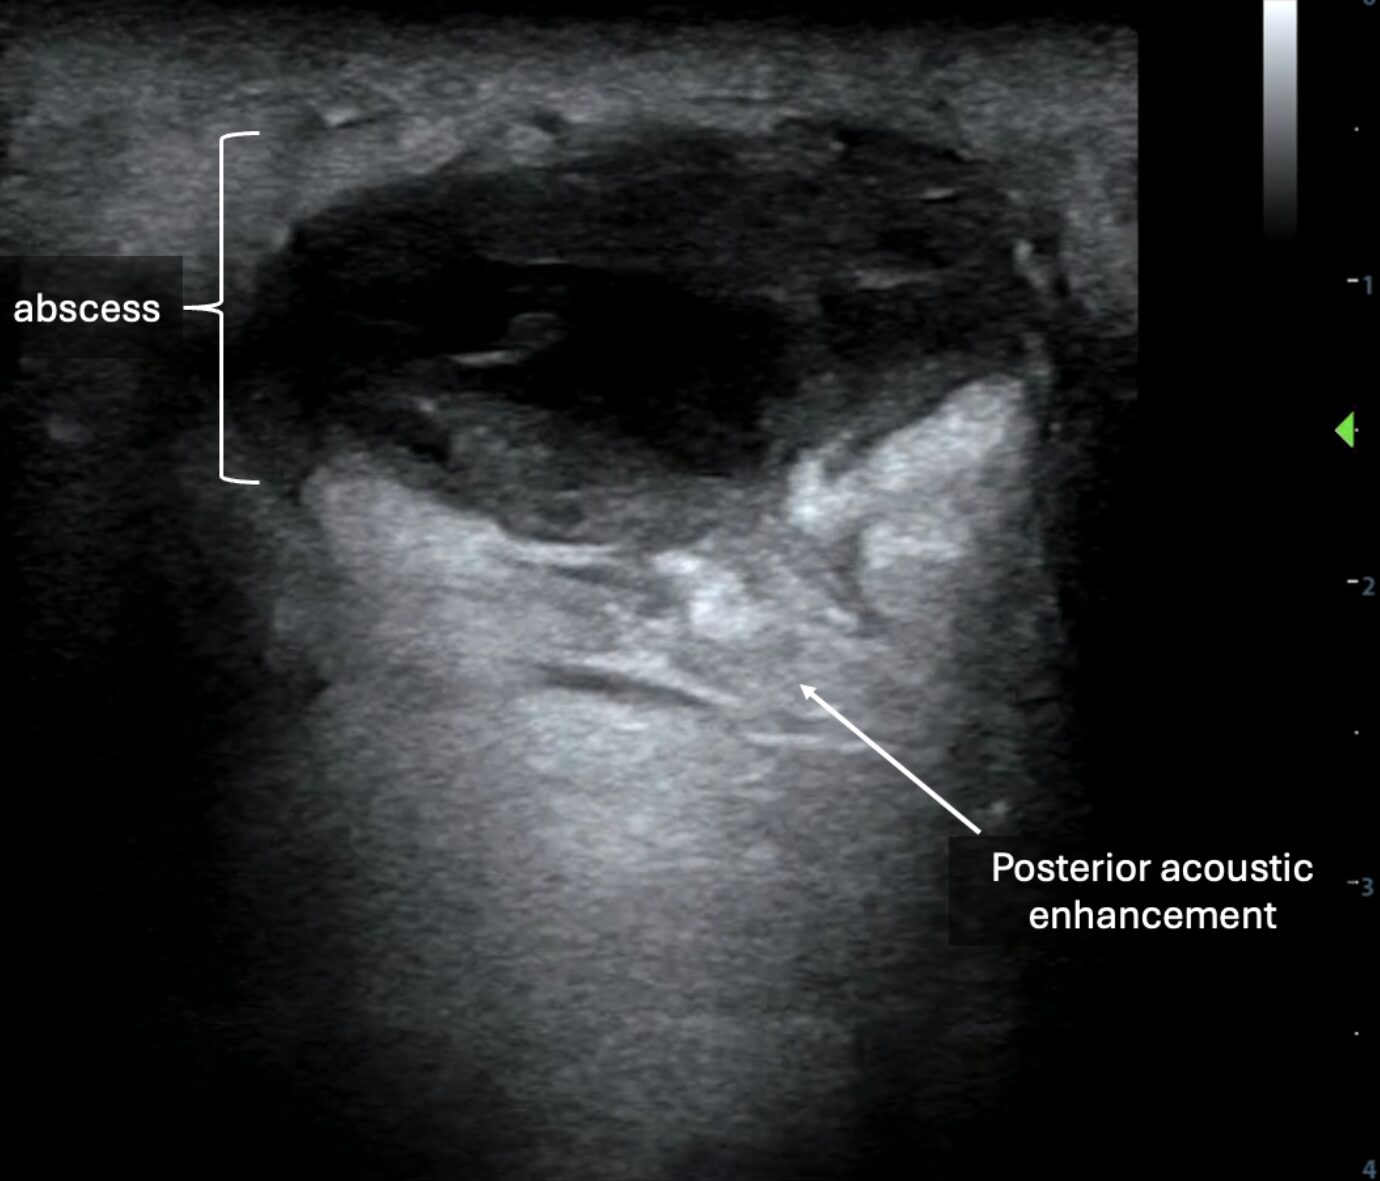

Sonographically, abscesses appear as collections of anechoic, hypoechoic, or heterogeneous material depending on the contents of the purulence. Often, there is notable posterior acoustic enhancement deep to these collections (Images 7-8, Video 6-7). Surrounding cobblestoning, as seen in cellulitis, may also be present. When downward, axial pressure is applied to the abscess using the probe, contents within the abscess may demonstrate a dynamic swirling motion referred to as “the squish sign” or “pus-istalsis” (Video 9).

Image 8: In later clinical stages, abscesses may appear as more well-circumscribed collections with posterior acoustic enhancement.

Video 7: Video of the above still image demonstrating an abscess.